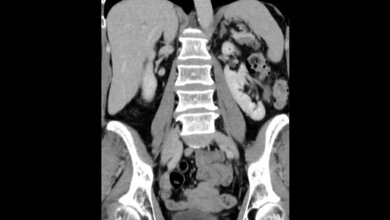

Wie läuft eine Lebendspende ab?

Prof. Werner: Nach vielen Monaten der Vorbereitung wird am Operationstag erst dem Spender eine Niere entnommen. Dies erfolgt in der Regel mit Hilfe der sogenannten Schlüsselloch-Technik, was die Wundheilung und die Erholung nach der Operation beschleunigt. Im Anschluss wird dem Empfänger die Niere in einer circa dreistündigen Operation transplantiert. Hierbei müssen die kranken Nieren des Empfängers nicht entfernt werden, die neue Niere wird links oder rechts neben der Blase in das kleine Becken eingesetzt.